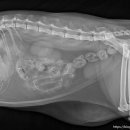

• 선부중앙동물의료센터 | 강아지 요로 결석 재발 재수술 후기

​ ​ ​ 강아지 결석 재발 재수술 후기 강아지 요로결석, 방광결석 재발로 재수술하게 된 후기 남겨봅니다. 반려견 결석은 재발률이 높은 편이라고 해서 꾸준히 관리...이번 수술은 선부중앙동물의료센터에서 진행했어요. ​ ​ ​ ​ 📍선부중앙동물의료센터 정보 주소 : 경기 안산시 단원구 선부광장1로 69 단지내상가동 2층...

참지않는 치와와(2026-03-28 13:21:00)